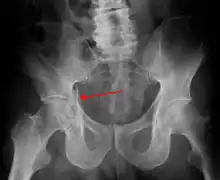

| Acetabular fracture as seen on plain X-ray |

| Posterior wall | This is the most common variety of acetabular fracture. It typically occurs due to dashboard injury; when a person travelling in a vehicle involved in a head-on collision, the force applied over the flexed knee travels along the femur bone to the head of the femur, breaking the posterior wall of the acetabulum. The head of the femur is dislocated outside the joint. | T shape | When a transverse fracture also had a vertical fracture line, it is called a T shape fracture. Here the innominate bone is broken in such a way that all three parts of it, the ilium, the ischium and the pubis are separated from one another. This is a three part fracture. Though both columns are broken, the weight bearing dome is still attached to the main part of the ilium and hence it is not a true fracture of both columns.

- Posterior wall fracture: Iliac oblique and obturator oblique views